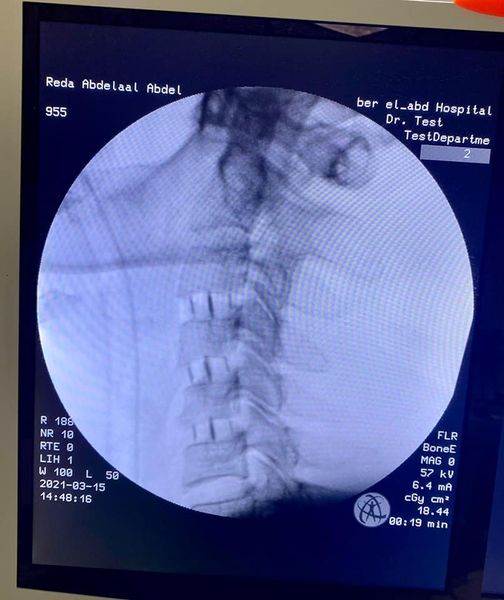

نجح الطاقم الطبي من أساتذة كليات الطب بالجامعات وفريق طبي من مستشفى بئر العبد المركزى فى اجراء عملية جراحية عاجلة وخطيرة لمريض كان يعانى من آلام بالرقبة مع خذلان شديد وضعف بالأطراف الأربعة نتيجة ضيق بالقناة العصبية العنقية وكدمة بالنخاع الشوكى ، وقد خرج المريض من المستشفى مع تحسن ملحوظ فى الحركة والخذلان .

وأعلن الدكتور تامر حمدى مدير إدارة المستشفى ( فى بيان ) أن الفريق الطبي قام بمجرد وصول المريض الى المستشفى باجراء جراحة عاجلة .. حيث تم استئصال ثلاثة غضاريف عنقية أمامية .. مع تركيب أقفاص كربونية للمريض البالغ من العمر ٤١ عاما ، وقد تحسنت حالته وأصبح قادرا على الحركة وتوقف الخذلان .. مشيرا الى أن جراحات الفقرات العنقية هى الأولى من نوعها بمستشفى بئر العبد المركزى ، وهى من أدق جراحات المخ والأعصاب والعمود الفقرى على الاطلاق.